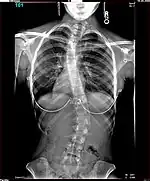

The Harrington Rod, or Harrington implant, is a device for the straightening of the spine inside the body, designed by Paul Harrington. The device consists of a stainless steel rod, attached to the spine at the top and bottom of the curve with hooks. Attached ratchets are then tightened to distract or straighten the spine. Following surgery to insert the rod, the patient wears a postoperative plaster cast or brace for a few months, until vertebral fusion has occurred, after which the cast or brace is removed.[5]